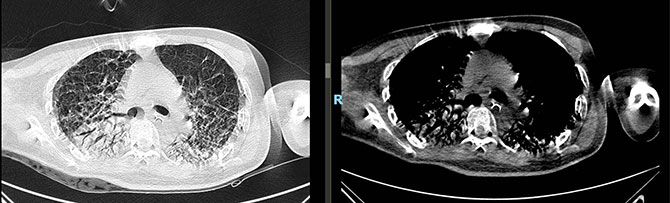

术前CT

术后CT